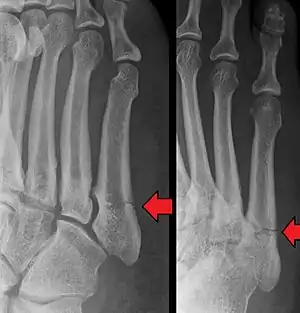

Jones fracture as seen on Xray

A Jones fracture is a broken bone in a specific part of the fifth metatarsal of the foot between the base and middle part[8] that is known for its high rate of delayed healing or nonunion.[4] It results in pain near the midportion of the foot on the outside.[2] There may also be bruising and difficulty walking.[3] Onset is generally sudden.[4]

The fracture typically occurs when the toes are pointed and the foot bends inwards.[6][2] This movement may occur when changing direction while the heel is off the ground such in dancing, tennis, or basketball.[9][10] Diagnosis is generally suspected based on symptoms and confirmed with X-rays.[3]

A person with a Jones fracture may not realize that a fracture has occurred. Diagnosis includes the palpation of an intact fibularis brevis tendon, and demonstration of local tenderness distal to the tuberosity of the fifth metatarsal, and localized over the shaft of the proximal metatarsal.

Diagnostic X-rays include anteroposterior, oblique, and lateral views and should be made with the foot in full flexion.

Pseudo-Jones fracture